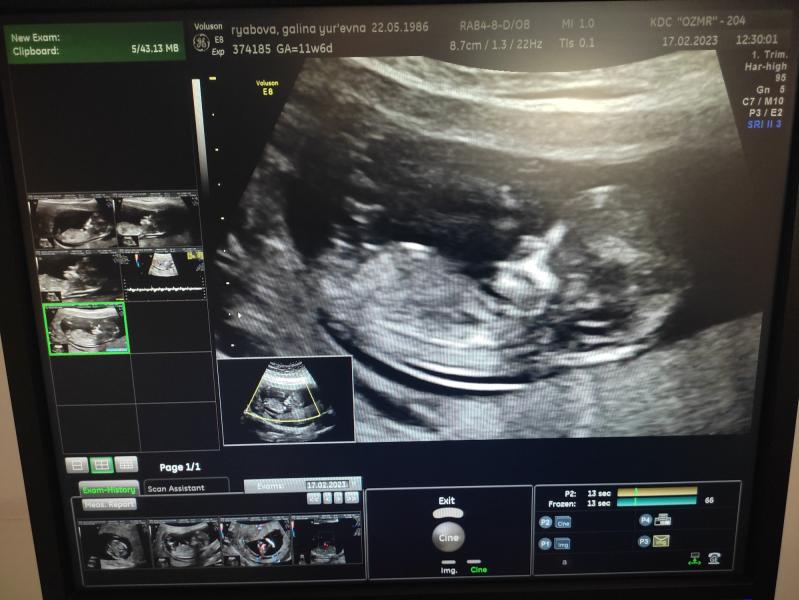

Сегодня ходила на первый скрининг! Врач никак не могла определить пол ребенка.Терпежа не хватает,как хочется знать.🥲🥲Может кто подскажет?😅

По вашему фото ничего не понятно ,врать не буду...моим прям "пипирку" приближали

На таком сроке не покажет. Только, в лучшем случае, после 13 недель и то, хороший специалист, т.к там нет ещё половых органов, а только небольшой бугорок у мальчиков😄

У вас фотка не между ног даже))) тут не определишь. На втором скажут точно, либо кровь сдать

Сдайте кровь на определение пола, на первом скрининге пол еще не возможно определить, только предположить